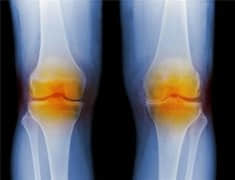

关于骨性关节炎的一些常见问题

膝盖疼很常见,如何判断是不是关节炎?